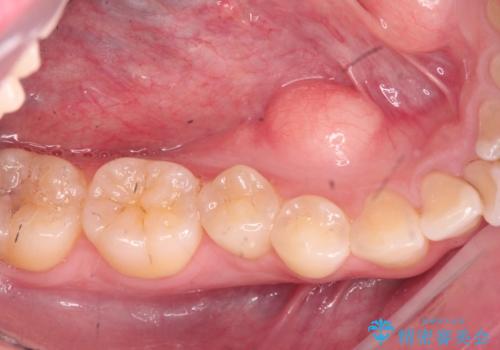

上下の歯のがたつきを改善するマウスピース矯正治療と、下顎に見られる大きな骨隆起を外科的に除去する治療計画を進めていきます。

骨隆起の除去は、静脈内鎮静法を用いてほとんど記憶のないうちに行うことができます。

歯並びが改善したとともに、骨隆起を除去したことで舌をしまうスペースも増え安定した口腔内環境を確立することができました。

- 外科手術のため、術後に出血、痛みや腫れ、違和感を伴います